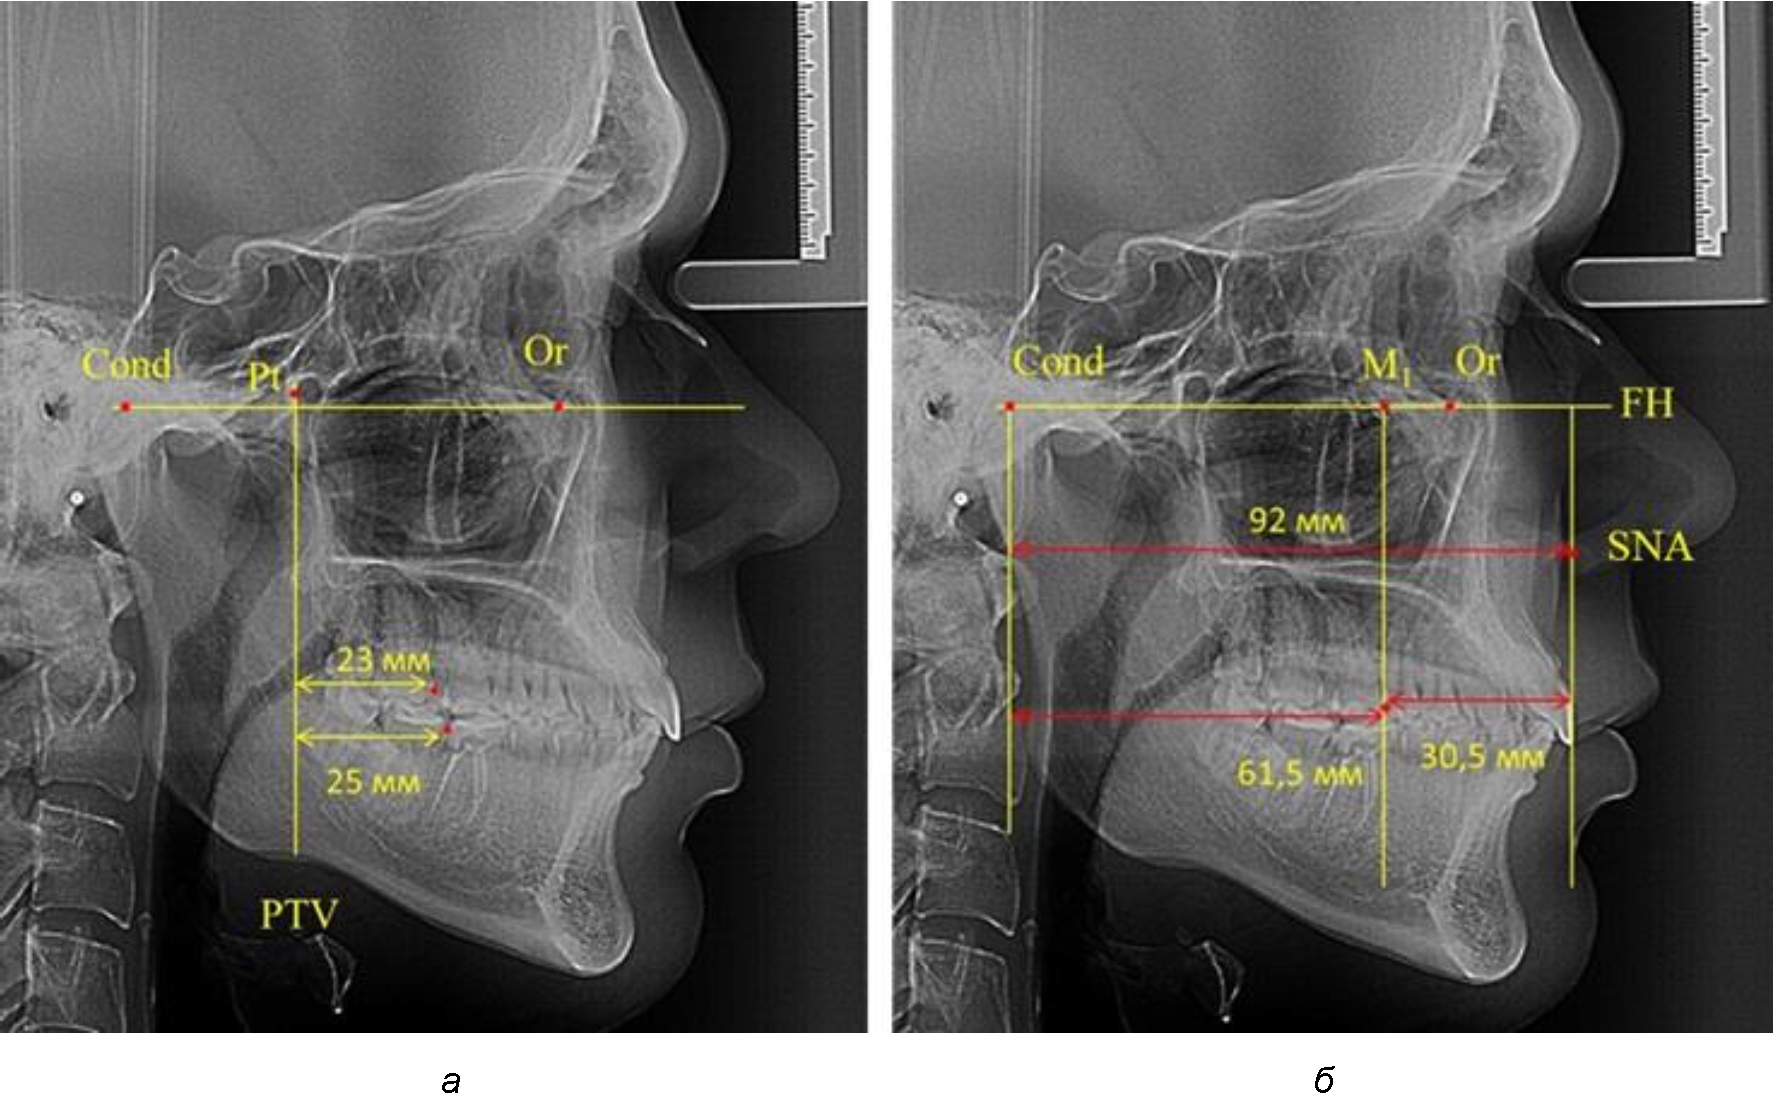

Второй частью исследования был анализ положения первых постоянных моляров в различные периоды сменного прикуса. На телерентгенограммах детей периода прикуса молочных зубов дистальная поверхность зачатка первого постоянного моляра отстояла от крыловидной вертикали на величину, составляющую около 7 мм, что было близким по значению к данным R. E. McDonald. Сагиттальный размер гантического отдела составлял около 60 мм, а его отношение к кондилярно-молярной глубине – 1,5 (рис. 4).

Рис. 4. Особенности положения первых моляров по R. E. McDonald (а) и по предложенному методу (б) у ребенка 4 лет